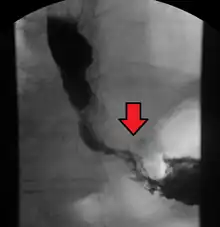

Esophageal cancer (lower part) as a result of Barrettʼs esophagus

Male predominance is particularly strong in this type of esophageal cancer, which occurs about 7 to 10 times more frequently in men.[25] This imbalance may be related to the characteristics and interactions of other known risk factors, including acid reflux and obesity.[25]

The long-term erosive effects of acid reflux (an extremely common condition, also known as gastroesophageal reflux disease or GERD) have been strongly linked to this type of cancer.[26] Longstanding GERD can induce a change of cell type in the lower portion of the esophagus in response to erosion of its squamous lining.[26] This phenomenon, known as Barrett's esophagus, seems to appear about 20 years later in women than in men, possibly due to hormonal factors.[26] Having symptomatic GERD or bile reflux makes Barrett's esophagus more likely, which in turn raises the risk of further changes that can ultimately lead to adenocarcinoma.[16] The risk of developing adenocarcinoma in the presence of Barrett's esophagus is unclear, and may in the past have been overestimated.[2]